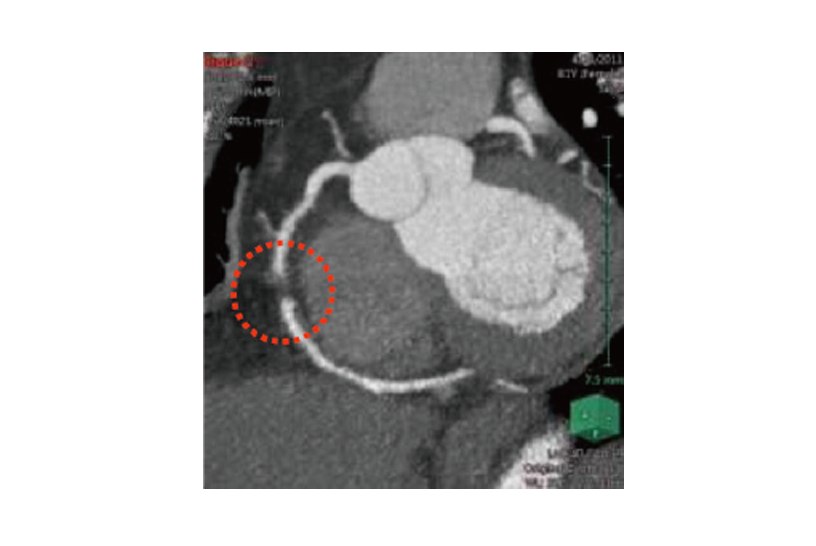

3D Imaging and Analysis System Volume Analyzer

Capable of precisely and accurately isolating sectors regardless of individual differences or widely-varied lesions or image qualities. Also compatible with unknown ailments, such as severed blood vessels.